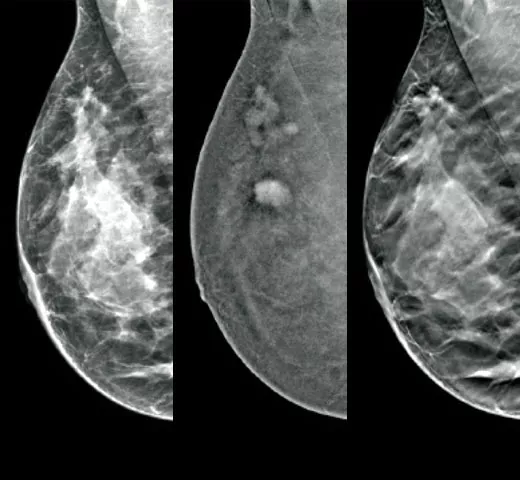

Cutting-Edge Imaging

Optimal cancer detection starts with high quality imaging. Integrate the EUREF-approved1 Hologic mammography technologies into your clinical pathway to maximise efficiency in your imaging workflow.

Confident Cancer Detection

The clinically proven tomosynthesis and contrast enhanced imaging technologies, plus future-proofed AI powered solutions at the point of care, help you make better clinical decisions while accelerating reading time and improving operational efficiency.

Clarity HD™ High Resolution Tomosynthesis

Producing high-resolution tomosynthesis images normally means slower read times. However, combining Clarity HD high-resolution 3D imaging with Genius AI Detection technology and 3DQuorum allows you to unleash fast and high resolution 3D images,5 accelerating screening and analysis.

Intelligent 2D™ Synthesised Imaging

For higher image quality, more detail, improved read times and low dose, this AI-powered software produces robust, yet natural looking, synthesised 2D images that are well correlated with the 3D mammography data. This enables radiologists to quickly and confidently see subtle mammography features and lesion morphology.